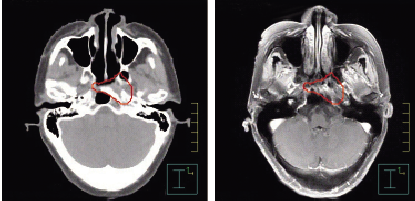

人工檢查完后再進行輔助機器檢查,CT顯示腦積水、雙側腔隙性腦梗死。?這個患者該怎么診斷?按照腹痛的九問九思,沒有發現對診斷有價值的線索,那就給患者開常規檢查,彩超,包括胃腸鏡檢查,除了胃鏡發現胃息肉,其他都無法解釋患者的腹痛。